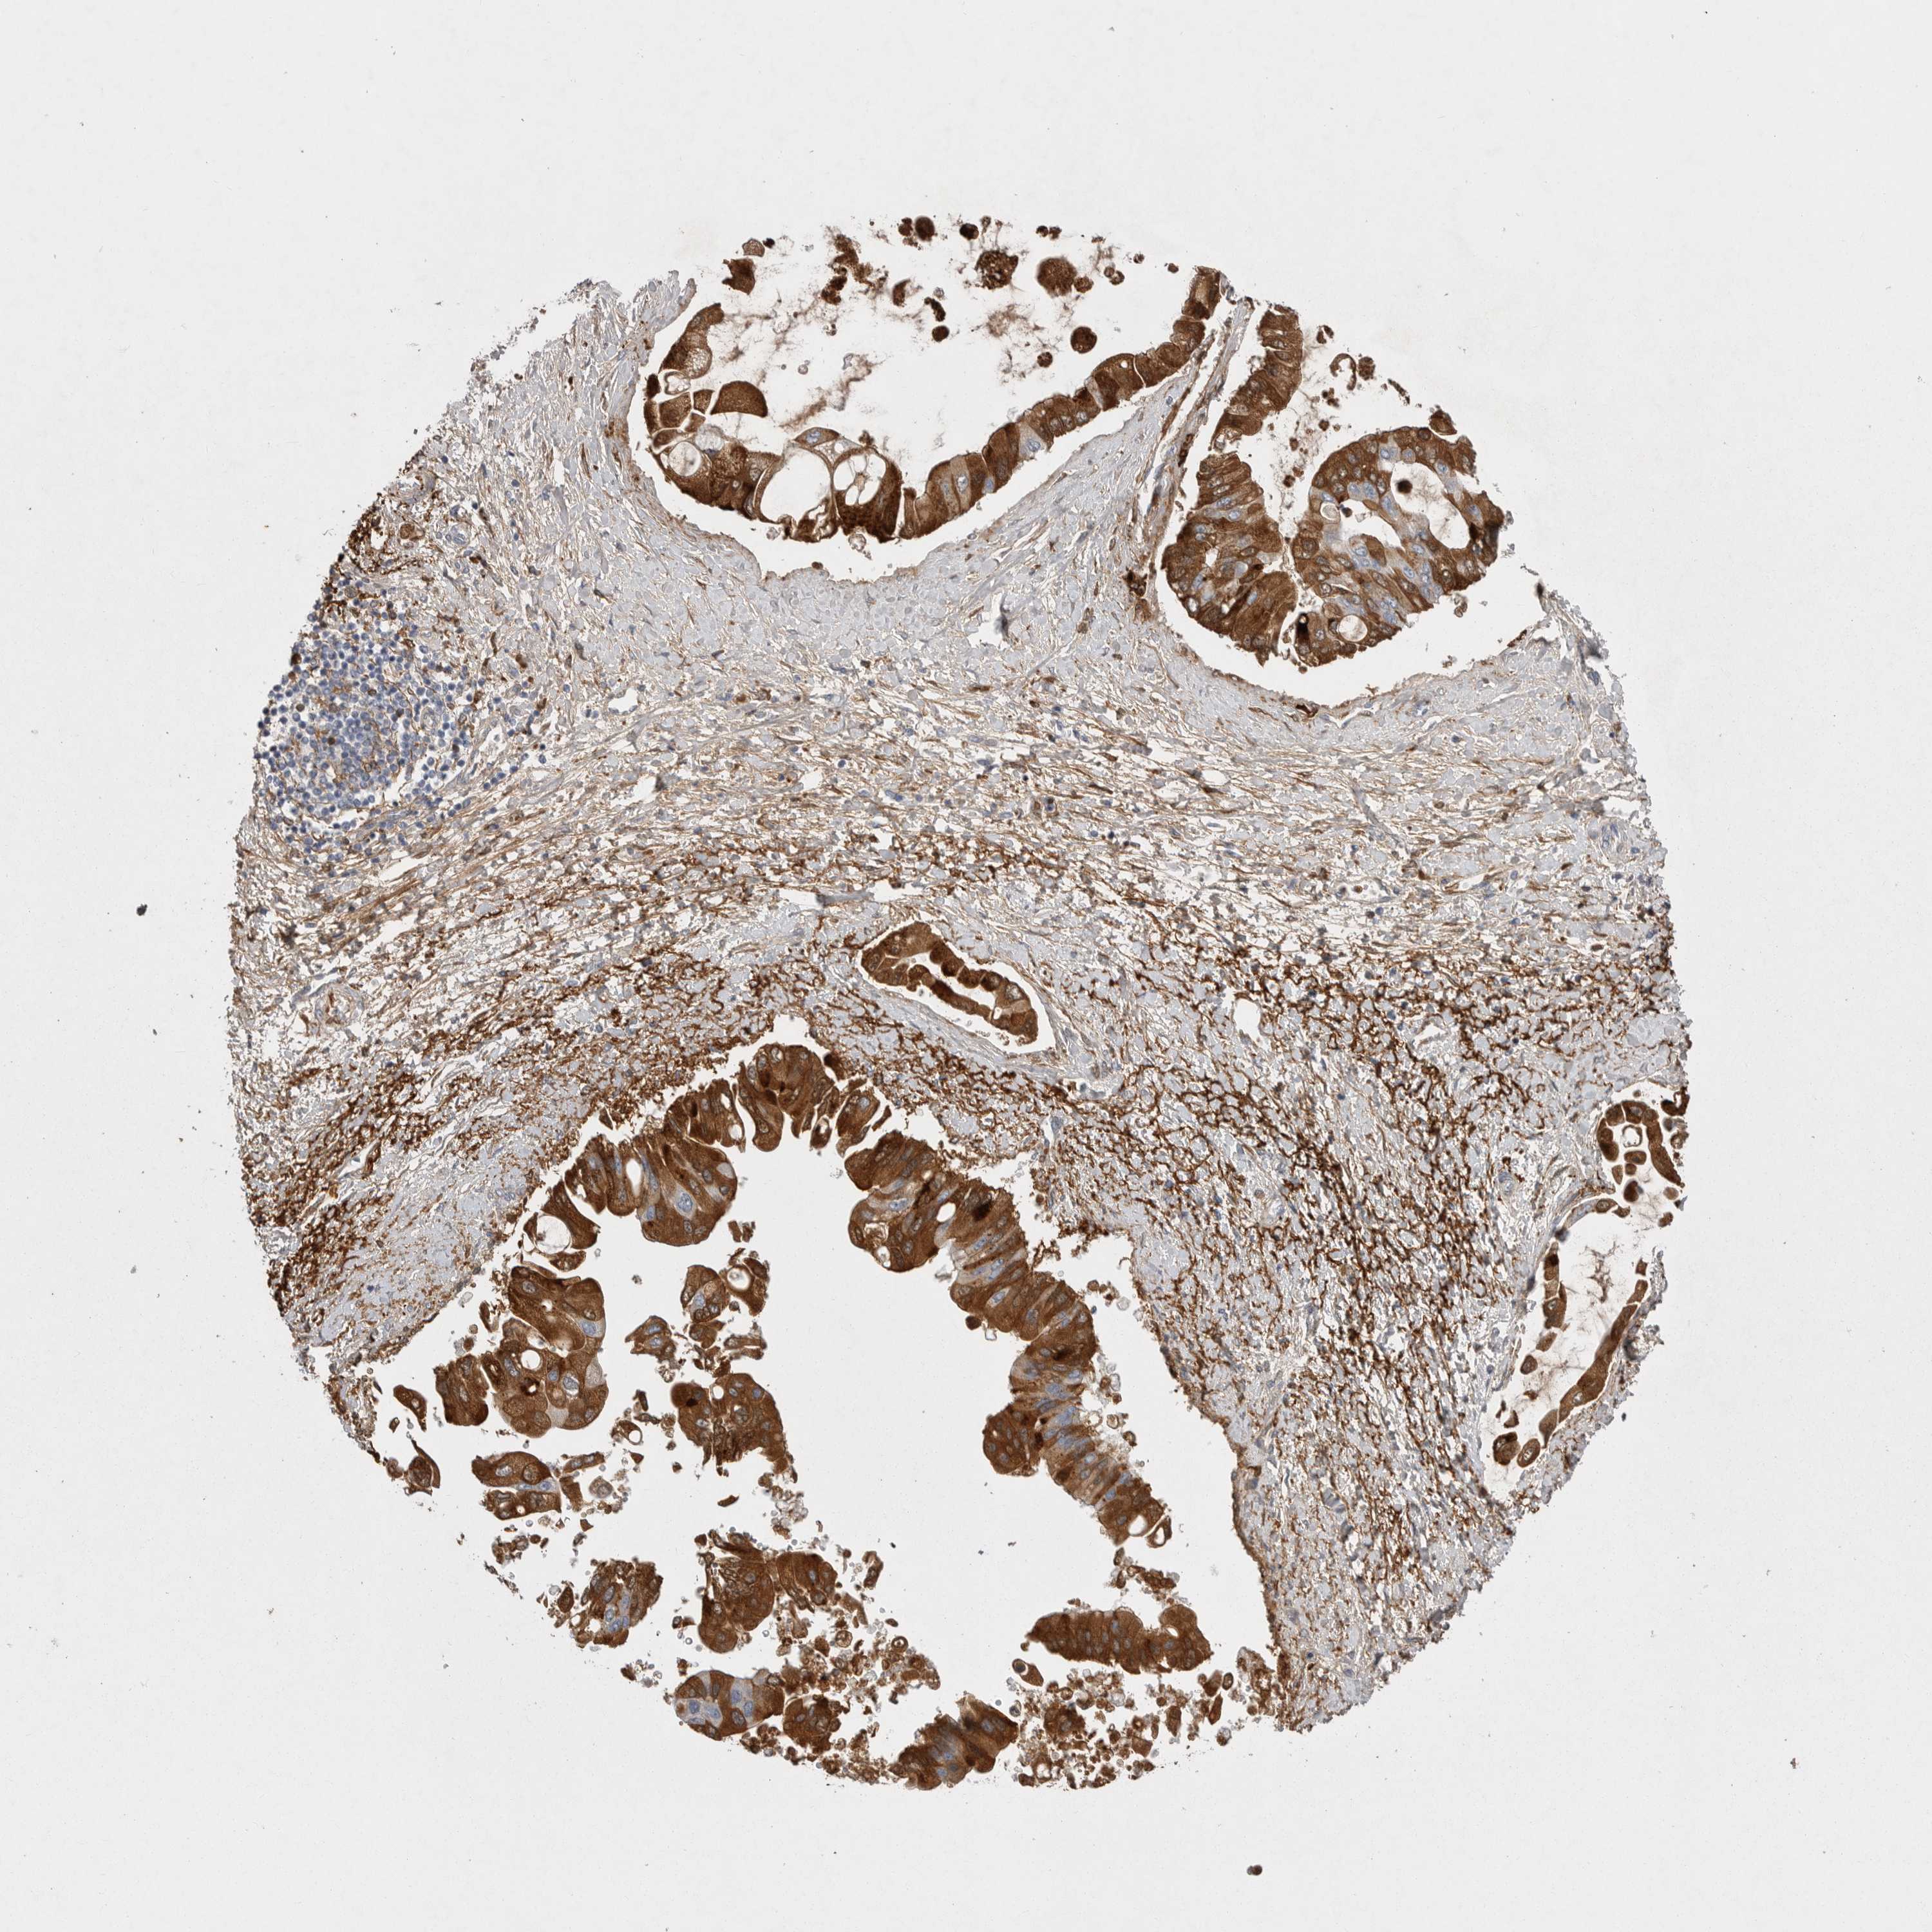

LIVER CANCER - Protein expressioni

A mouse-over function shows sample information and annotation data. Click on an image to view it in a full screen mode. Samples can be filtered based on level of antibody staining by selecting one or several of the following categories: high, medium, low and not detected. The assay and annotation is described here.

Note that samples used for immunohistochemistry by the Human Protein Atlas do not correspond to samples in the TCGA dataset.

Antibody stainingi

Antibody staining in the annotated cell types in the current human tissue is reported as not detected, low, medium, or high, based on conventional immunohistochemistry profiling in selected tissues. This score is based on the combination of the staining intensity and fraction of stained cells.

Each image is clickable and will lead to virtual microscopy that enables deeper exploration of all samples and also displays staining intensity scores, fraction scores and subcellular localization as well as patient and tissue information for each sample.

Antibody HPA027367

Antibody HPA027396

Antibody CAB005036

Staining

High

Medium

Low

Not detected

Intensity

Strong

Moderate

Weak

Negative

Quantity

>75%

75%-25%

<25%

None

Location

Nuclear

Cytoplasmic/membranous

Cytoplasmic/membranous,nuclear

Cholangiocarcinoma

Carcinoma, Hepatocellular, NOS